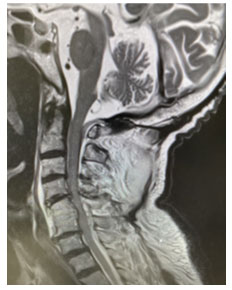

脊椎は幾つもの骨が連なって出来ています。首の部分にある頸椎から始まり、胸椎、腰椎、仙椎、尾椎から成り立っています。この脊椎の中の脊柱管には脊髄が通っており、末梢神経に繋がっています。脳から発せられる指令を全身に伝える神経や、逆に感覚の情報を脳へと返す神経、心臓や消化器などの運動を調節する神経など、いろいろな神経が走っているので、脊椎・脊髄の病気になると、様々な神経障害が起こります。